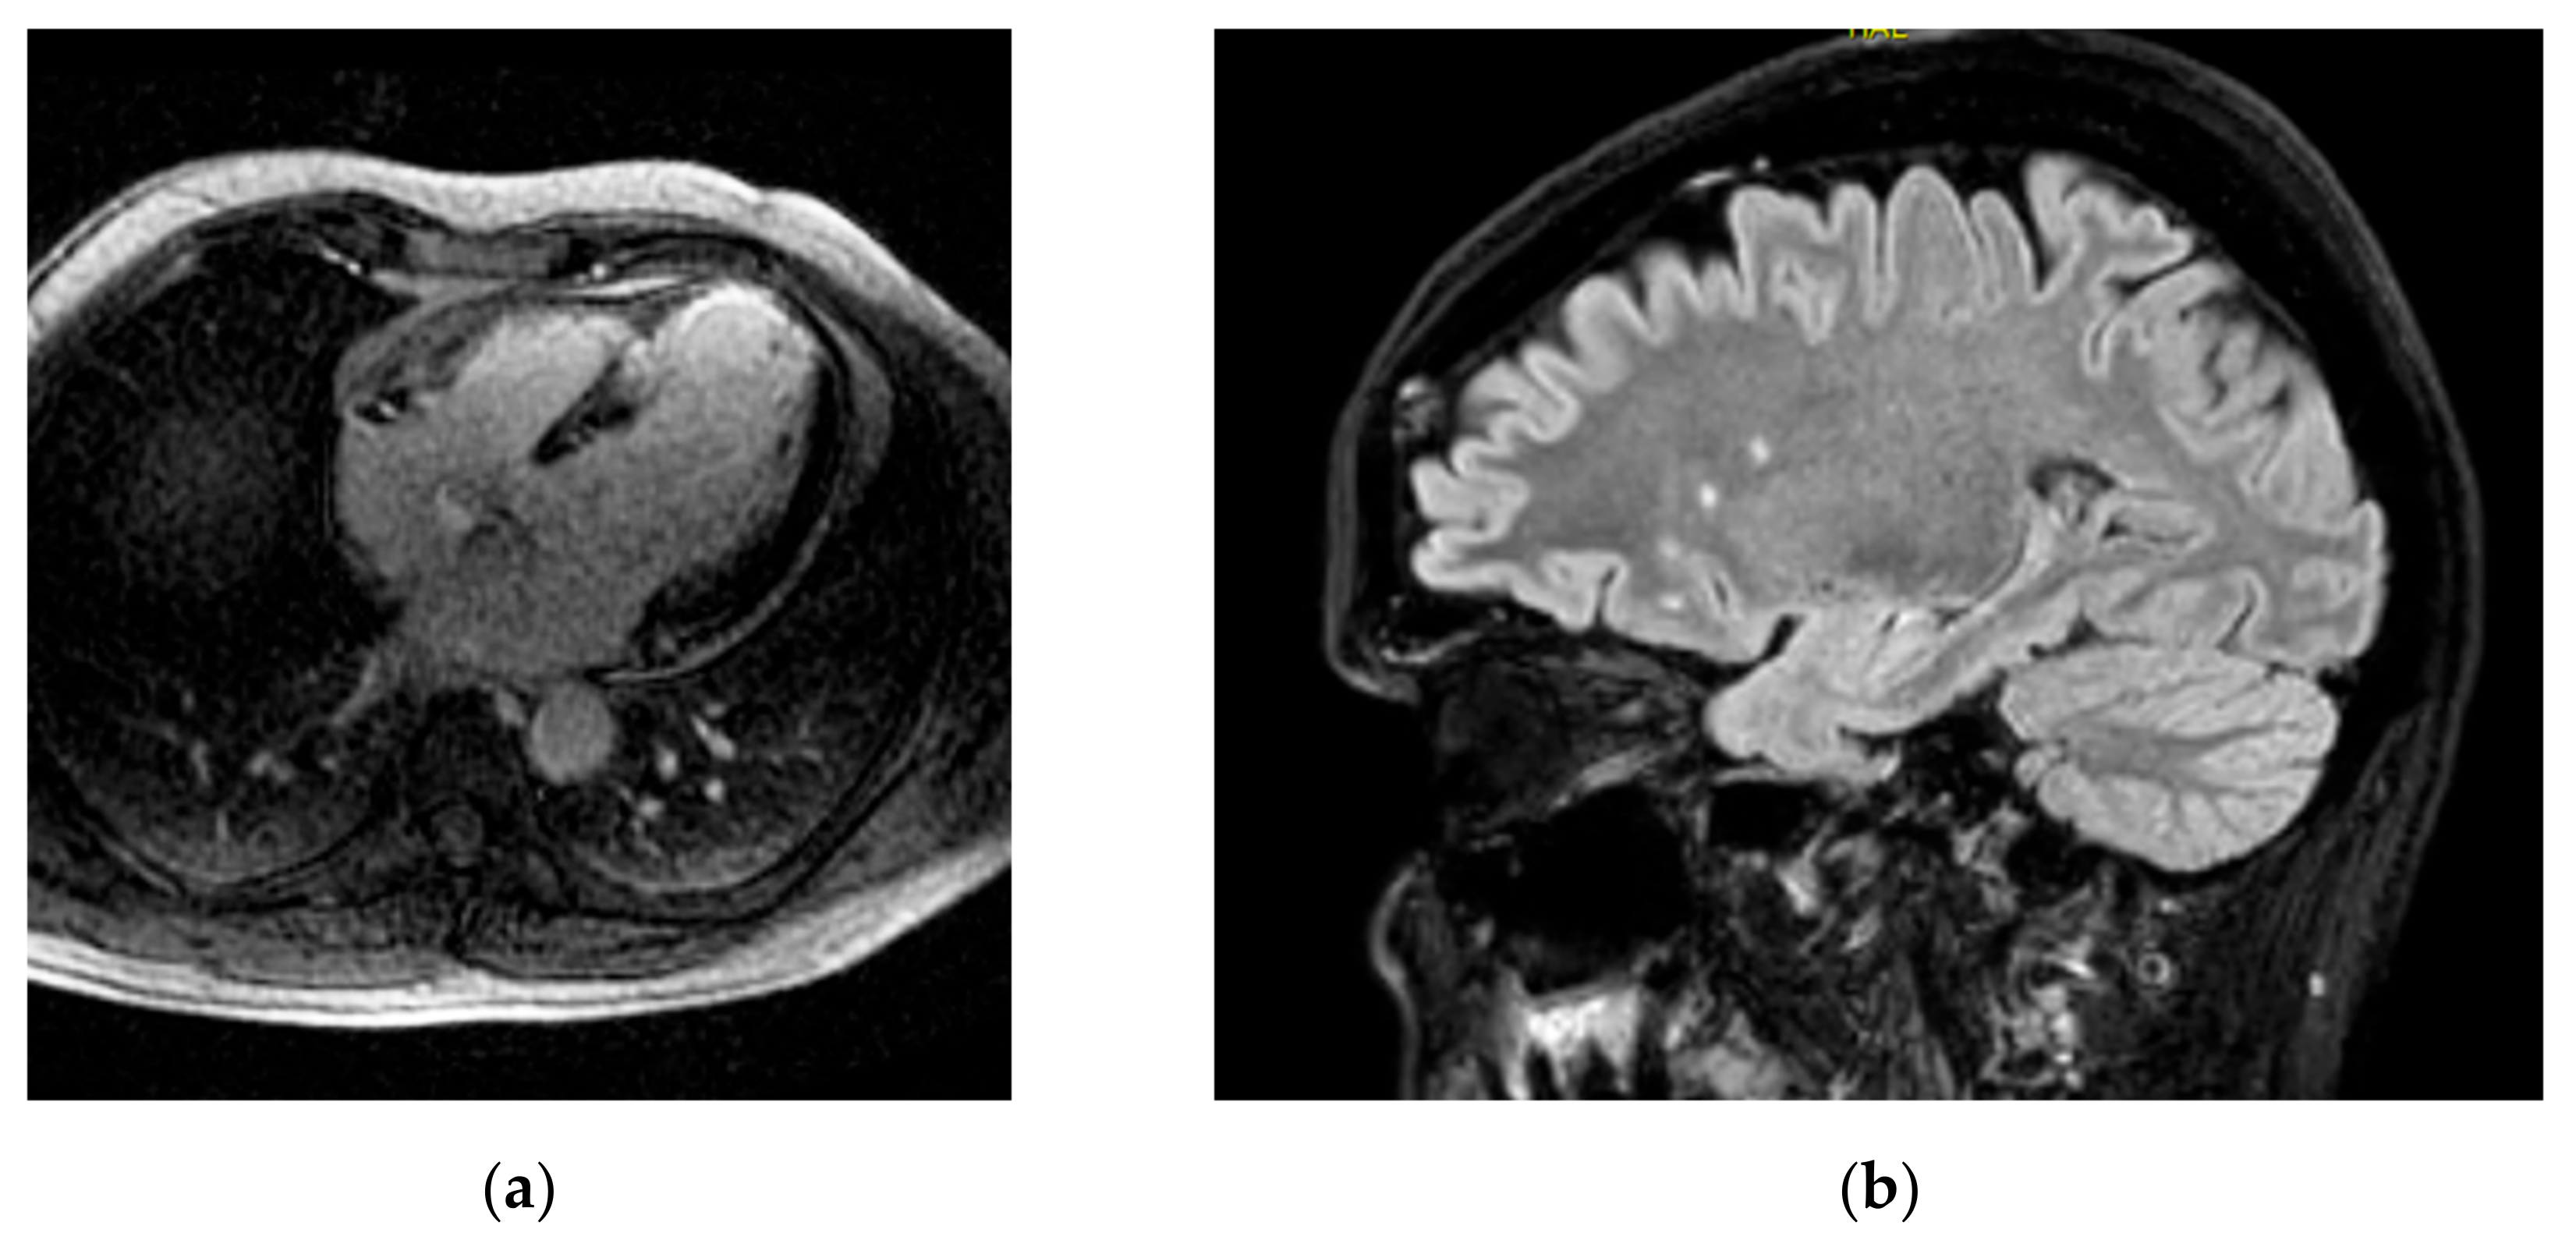

洋書 Cardiovascular Magnetic Resonance, 2e Open access information - Journal of Cardiovascular Magneticの詳細情報

Open access information - Journal of Cardiovascular Magnetic。洋書 Cardiovascular Magnetic Resonance, 2e Cardiovascular。洋書 Cardiovascular Magnetic Resonance, 2e Cardiovascular。

Society for Cardiovascular Magnetic Resonance/European

Society for Cardiovascular Magnetic Resonance/European